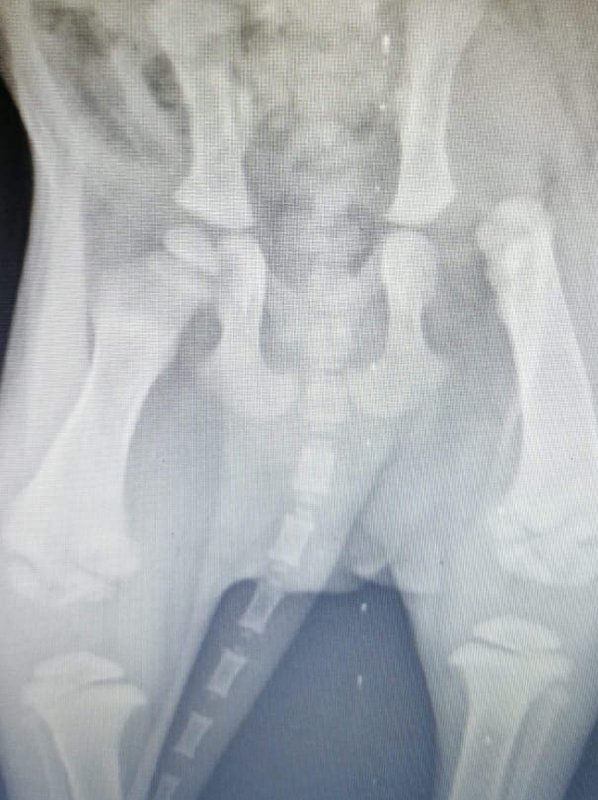

Es geht um kleine Babys, für die jede Hilfe zu spät kam, die aber vielleicht nicht hätten sterben müssen, wenn sie gleich in die richtigen, in Ritas Hände, gekommen wären ... - und um die Hoffnung für einen Welpen, den kleinen Spirit, der sich langsam Schritt für Schritt erholt und ins Leben kämpft - als das Schicksal sehr grausam noch einmal zuschlägt und wir eine niederschmetternde Diagnose von einem der Tierärzte bekamen, mit einem Röntgenbild, auf dem nichts Gutes zu sehen war ...

Mit einem Schreck haben die Tierschützerinnen gesehen, dass Spirit nicht richtig laufen kann und Susi fuhr mit dem kleinen Kerl zur besten Tierklinik im Umkreis. Spirit wurde geröntgt und dabei hat der Tierarzt festgestellt, dass ihm die Hüftpfanne fehlt! Was das Leben alles bereit halten kann für so eine kleine unschuldige Seele ist echt grausam! Spirit muss nun einfach älter werden, so 6-7 Monate, und die Wachstumsfugen müssen sich schließen, dann kann man erneut ein Röntgenbild machen und sehen, ob operativ etwas zu tun ist. Noch denken wir, dass er keine gravierenden Schmerzen hat, aber ohne was zu tun werden die sicher kommen. Inzwischen kommt Spirit - noch ohne OP - und mit Nahrungsergängungsmitteln für Knochen, Muskulatur, Sehnen und Bänder ganz gut zurecht. Er steigt sogar schon einzelne Treppen hoch und bewegt sich recht flott im Feld bei dem Welpenkennel mit den anderen Welpen. |